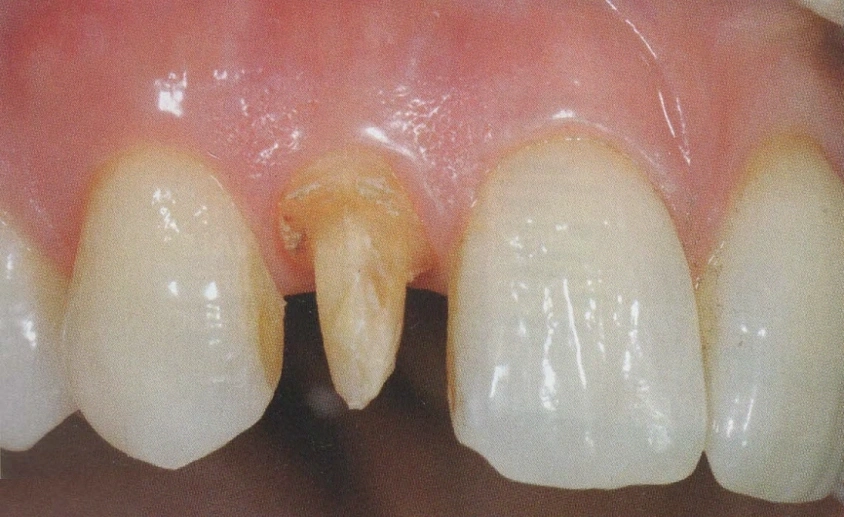

In questo studio vengono eseguite ceramiche di ultima generazione quali la zirconia ceramizzata, le ceramiche estetiche in disilicato senza trascurare le tradizionali metalceramiche. Il disilicato è un materiale altamente estestico che conferisce alla corona protesica un aspetto naturale e con questo materiale si possono creare manufatti con uno spessore molto ridotto.